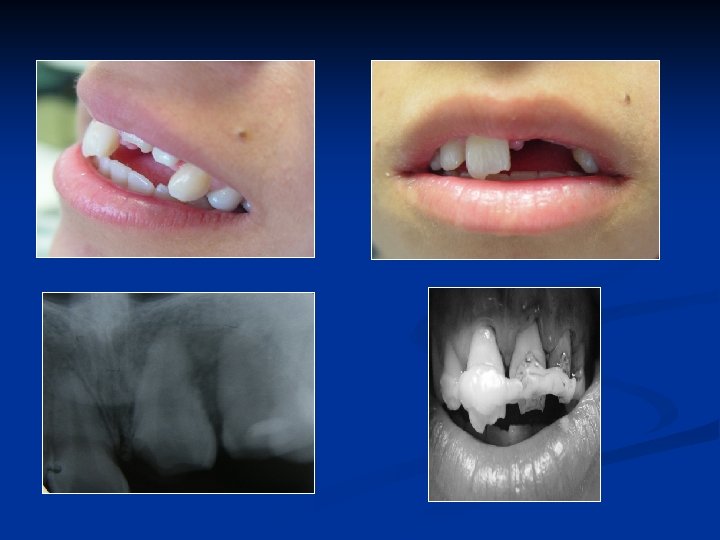

2 -LOKAL FAKTÖRLER A-Gömülü dişler: Ø Nitzen ve arkadaşları gömük dişlerin %7. 5 oranında komşu dişlerinin köklerini rezorbe ettiğini, bunun 21 -30 yaşlardaki bireylerde en yüksek oranda görüldüğü ve erkeklerde kadınlarınkine oranla 2 kat daha fazla geliştiğini belirtmişlerdir. Ø Rezorbsiyon kenarı ile sürmemiş dişin kronunu arasında granülasyon dokusu bulunur. Sürmemiş dişin kronun çeperindeki incelmiş mine epiteli kronun rezorbsiyonunun engeller. Buna karşın basınç yaptığı dişin kökü rezorbe olur.